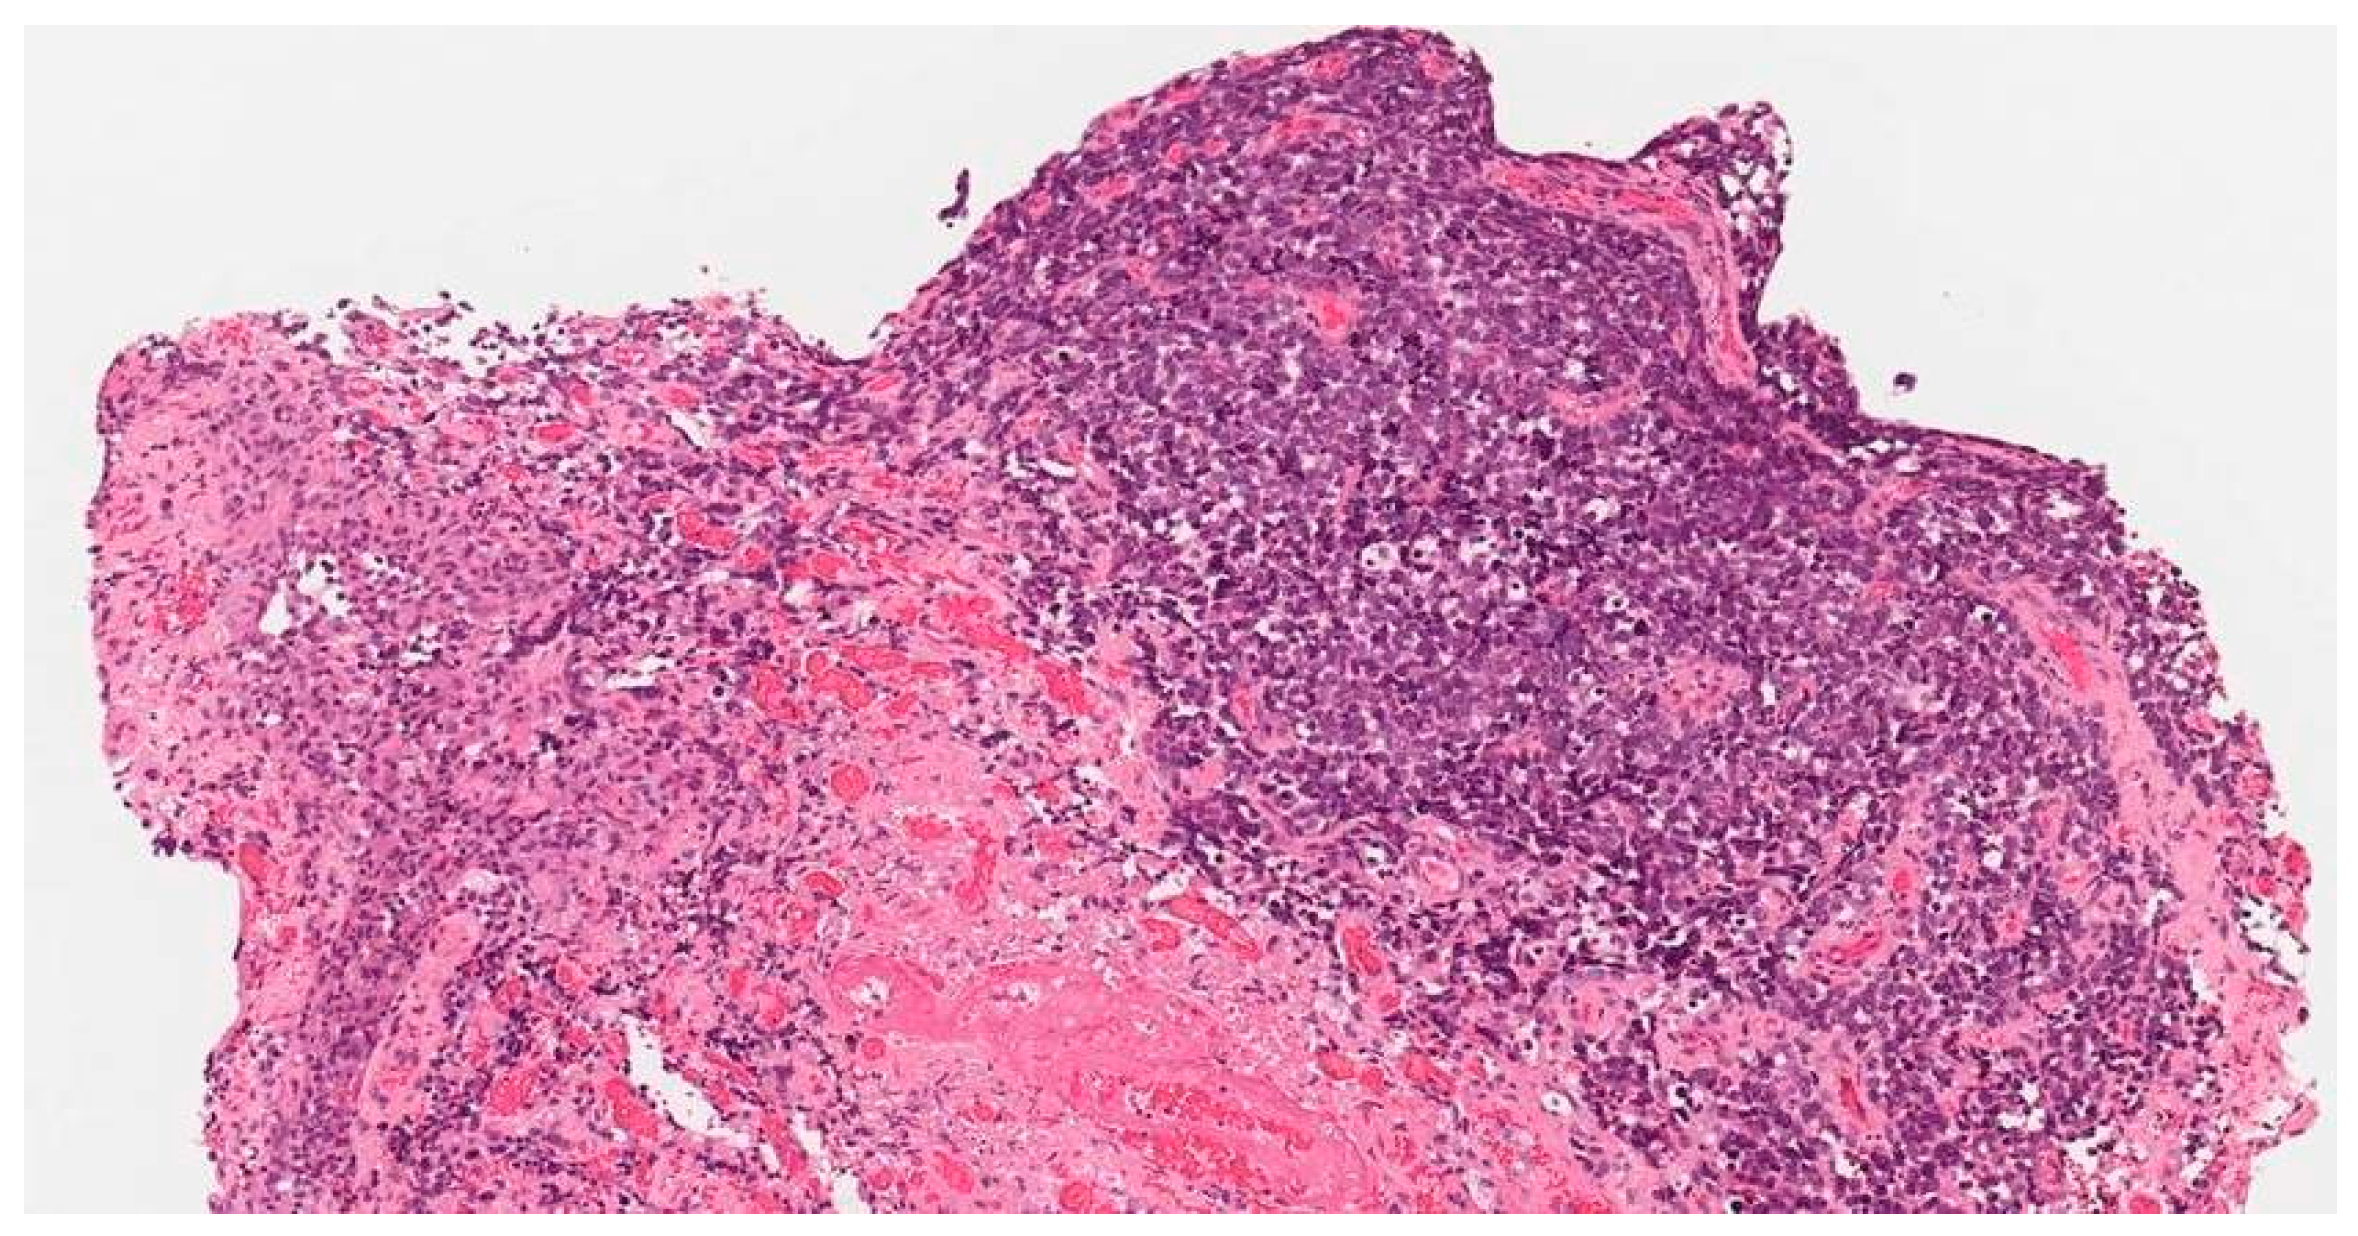

Multiple Rare Primary Malignancies: A Mixed Squamous Neuroendocrine Adenocarcinoma of the Cervix, Metastasized Carcinosarcoma and Extramammary Vulvar Paget’s Disease Case Report

2. Case Report